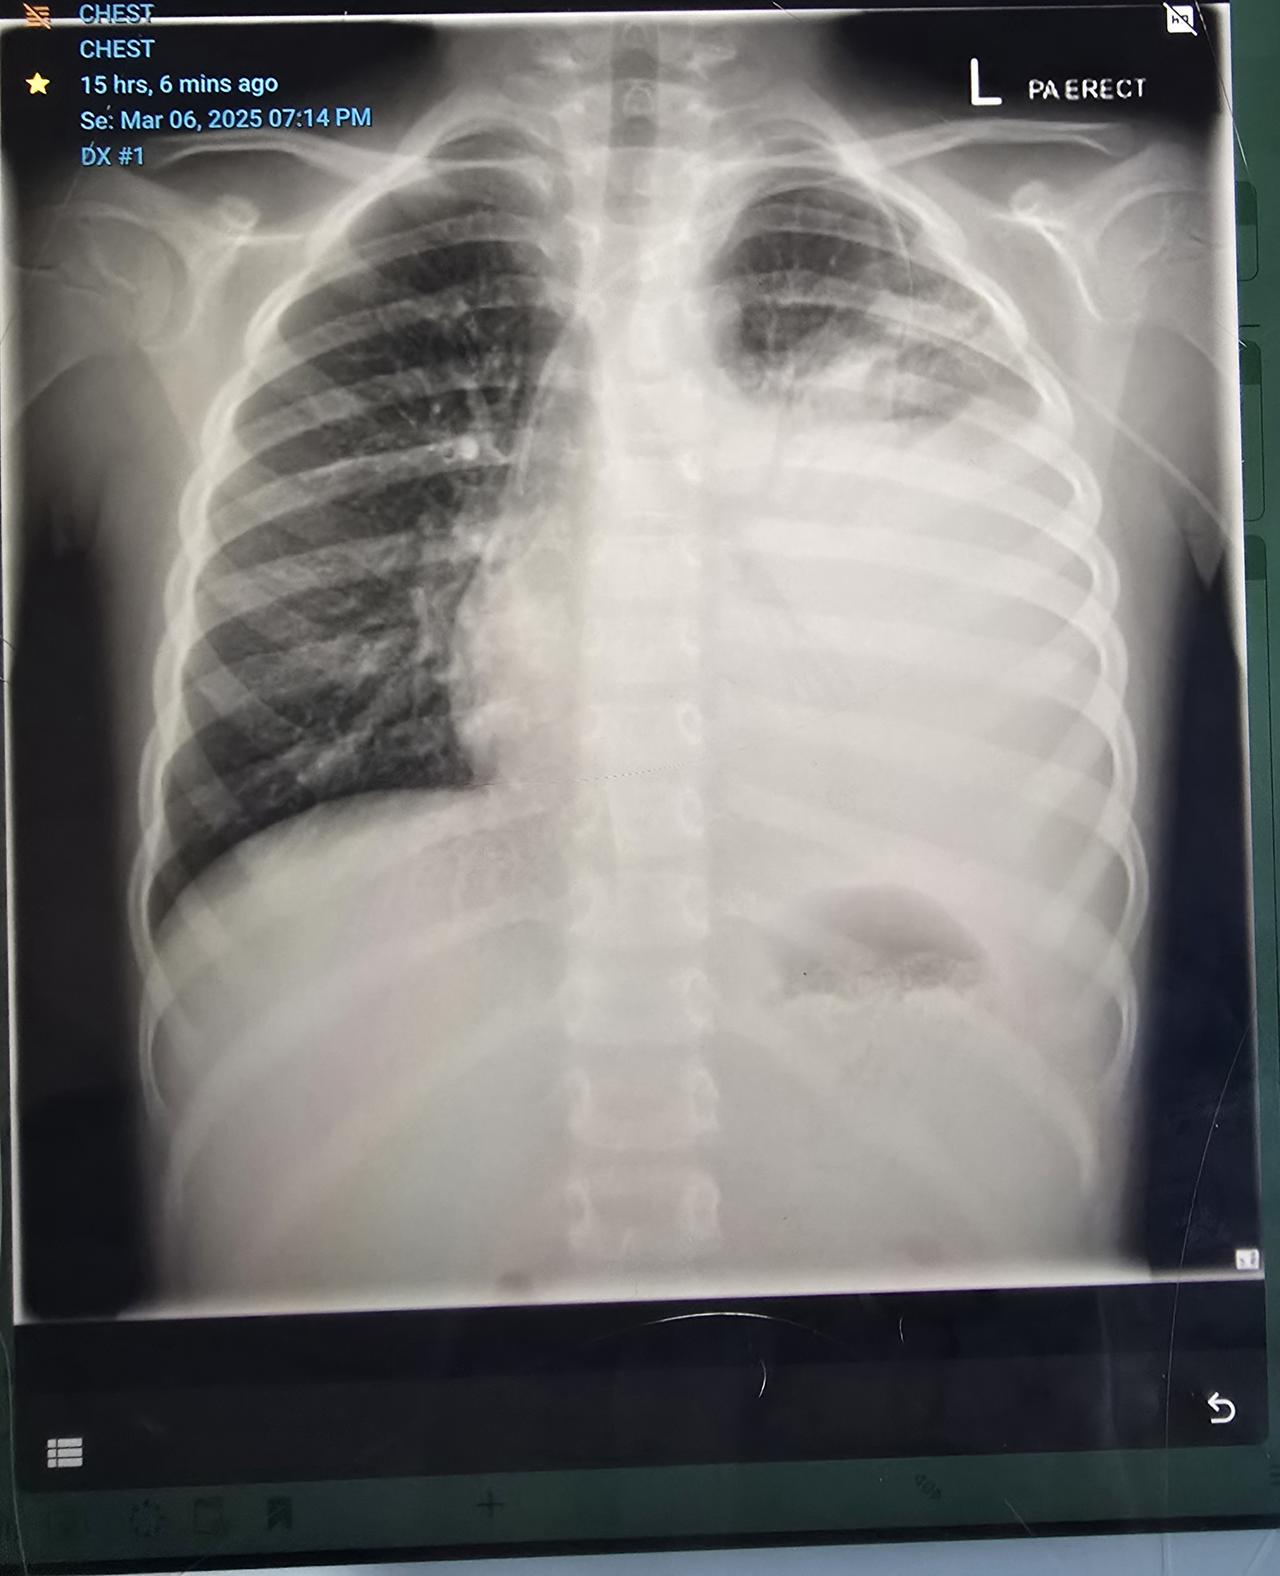

Main image

Connors breathing and general wellness was changing causing worry, upon Connors xray they found that his lung had completely filled up causing it to put pressure on surrounding organs. With oxygen levels dropping and increasing heart rate he will be getting another chest drain of approximately 500ml as they don't want to shock his body by removing it all. Scary times watching monitors and a genuinely unwell boy :(

While starting all the transplant tests it was picked up on a echo (heart test) that Connors chest sounds weren't quite right. After a xray it appeared Connor had 2/3 of his lung covered by fluid between lung and chest wall. Cause unknown however a drain was run the next day where they pulled out 900ml of fluid. It doesn't seem to be refilling at this stage however until this clears itself completely other treatments etc isn't an option. Still awaiting other test results to determine exact details 😞